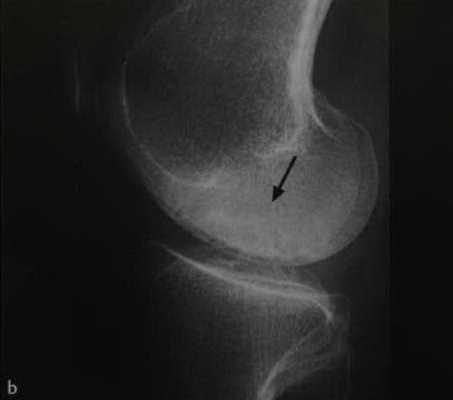

а-d Остеонекроз коленного сустава у женщины 65 лет. Внезапное возникновение болевого синдрома без травмы. Рентгенологическое исследование коленного сустава: (а) в прямой проекции, (b) в боковой проекции. Рентгенопрозрачные участки (стрелка) с окружающим склерозом, дегенеративными изменениями и уплощение суставных поверхностей.

(с), (d) МРТ. Фронтальное протонное плотно-взвешенное изображение с подавлением МР-сигнала от жировой ткани (с) и сагиттальное Т1 -взвешенное (d) изображение. Перифокальный отек и линейные субхондральные участки являются признаками стрессового перелома с дегенеративными изменениями в медиальном мениске.